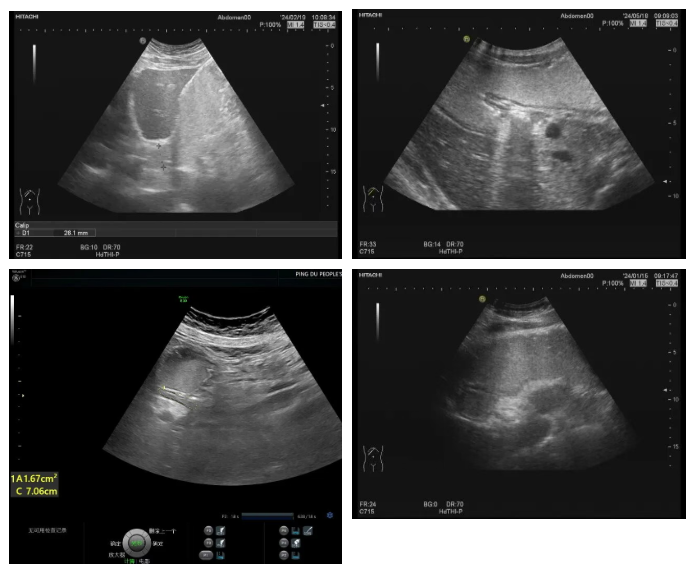

这是一种创新性的无创影像学检查技术。它无需插管,无需麻醉,患者只需口服一杯由天然食材精制而成的“超声造影剂”,该制剂口感宜人,安全无副作用。饮用后,造影剂能均匀充盈胃肠腔,有效消除胃肠内气体干扰,在超声探查下,清晰显示胃肠壁的层次结构、蠕动情况及周围毗邻关系,从而对病变进行精准评估。

层次分明:能清晰显示胃壁五层结构,有助于判断病变的起源、深度和性质,对黏膜下肿瘤、胃壁增厚性病变的显示具有独特优势。